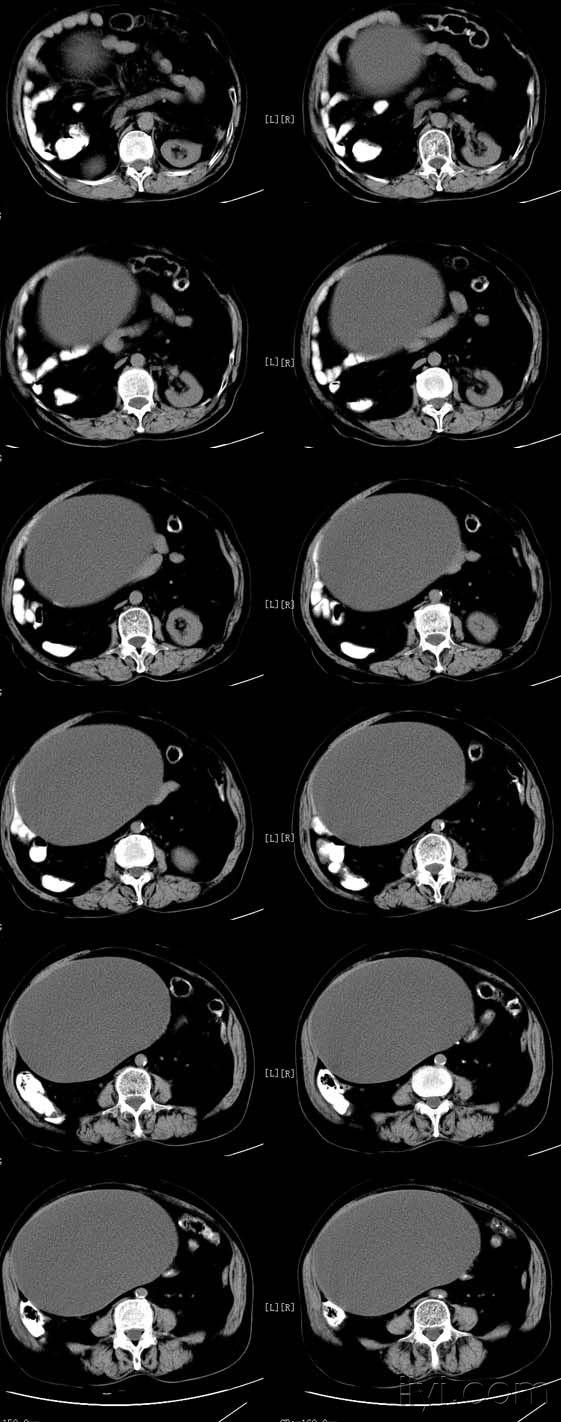

盆腔病变(卵巢乳头状浆液性囊腺瘤 )

诊间日记巨大卵巢交界性囊腺瘤

图片尺寸828x1104